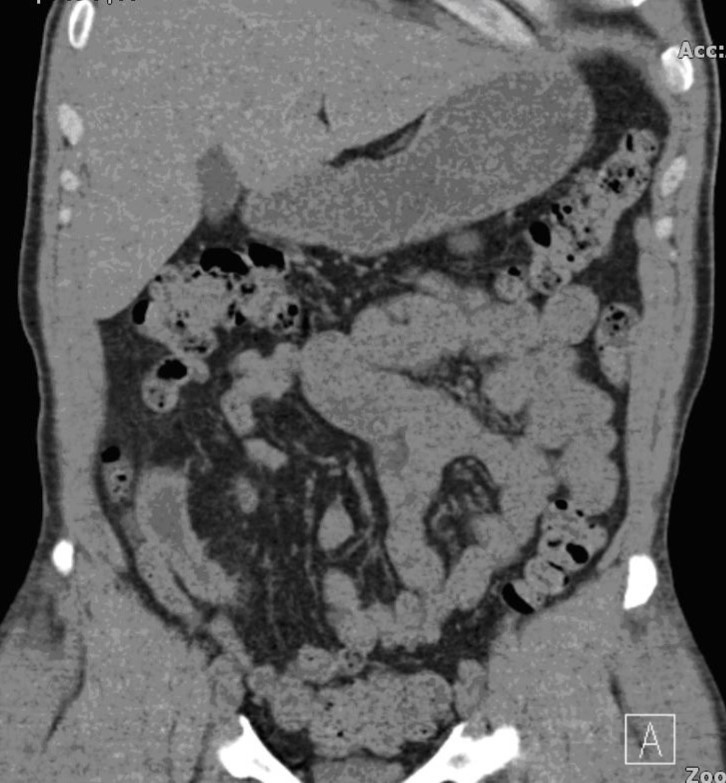

We report a case of a gentleman with spina bifida who underwent urinary diversion in the form of an ileal conduit as a child and presented 40 years later with worsening renal function that was picked up by his general practioner during routing investigations. Clinical examination revealed a hard mass superomedial to the right parararectal stoma. An initial ultrasound scan showed bilateral hydronephrosis and a possible calculus in the conduit. A subsequent CT KUB showed a 13 cm x 4 cm calculus occupying most of the conduit causing outflow obstruction (Figure 1). He also had a 2cm left renal calculus. Following a Foley catheter insertion into the stoma under image guidance, his renal function returned to normality. The patient was counselled for both the open and endoscopic approach.